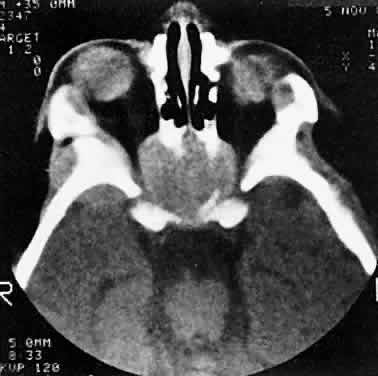

RHABDOMYOSARCOMA Rhabdomyosarcoma is the most common soft-tissue sarcoma in patients younger than 15 years of age and the most common primary orbital malignancy in childhood. These facts should not imply its frequent occurrence. Including all body sites, the annual incidence of childhood rhabdomyosarcoma in the United States is approximately 225 cases.2 The orbit is the site of origin in 5% to 25% of cases.3,4 However, site distribution varies with age. In children 5 to 9 years of age, for example, approximately 40% of primary rhabdomyosarcomas involve the orbit or eyelid.2 Although relatively rare, the tumor has a devastating natural history and demands a high index of suspicion in all cases of pediatric proptosis. Orbital rhabdomyosarcomas are slightly more common in females, with a 0.79 to 1 male-to-female ratio.2 The average age of presentation is 7.8 years, but the tumor may be present at birth and has been reported in patients as old as 78 years.5 A positive family history and associated anomalies have at times been identified, but these are exceptions rather than the rule. Classically, orbital rhabdomyosarcoma presents in an abrupt manner, with rapid progression of proptosis over days to weeks. A somewhat more indolent course does not exclude the diagnosis, however. Vigilance also should be exercised when rapidly expanding eyelid lesions are encountered. Rhabdomyosarcoma may present as ptosis or an eyelid mass rather than with proptosis.4 An eyelid rhabdomyosarcoma can occur as a congenital lesion.6 Within the orbit, rhabdomyosarcoma occurs most often, but not exclusively, in the superior nasal quadrant, with downward and outward displacement of the globe. CT scans show the topography of the orbital mass (Fig. 1A), as well as the possible extension into adjacent bone, paranasal sinuses, or the intracranial cavity. The circumscription that may be noted on CT is relative, because the lesion is not encapsulated and microscopically infiltrates normal tissue. Echography shows internal echoes of low-to-medium amplitude. Because the cellular tumor absorbs acoustic energy, the amplitude of the spikes falls off somewhat through the lesion (see Fig. 1B and C). MRI can help define the tumor's relationship to extraocular muscles (Fig. 2). The clinical diagnosis must be confirmed by biopsy. Because of the risk of seeding the biopsy tract, a transcranial approach should be avoided. If possible, the periosteum should not be violated because it presents a relative barrier to tumor invasion. Depending on its location, the lesion should be approached transconjunctivally or with an eyelid crease incision/transseptal dissection. The surgeon must balance the benefit of complete gross tumor resection with the risks of functional impairment and tumor dissemination that may accompany that effort. Tissue samples should be fixed in formaldehyde solution and glutaraldehyde for light and electron microscopic study. In addition, the value of immunohistochemical differentiation has been established for some time, and the potential uses of molecular genetic studies are rapidly emerging. Consequently, the procurement of fresh or frozen tissue, or both, has been given the highest priority by the Biopathology Discipline within the Intergroup Rhabdomyosarcoma Study Group (IRSG).2 These techniques can facilitate the diagnosis of poorly differentiated tumors, and they may refine diagnostic and prognostic classifications, identify candidate genes, and contribute to potential gene therapies. Since the inception of IRSG-I in 1972, the multicenter collaboration has enrolled the overwhelming majority of patients diagnosed with rhabdomyosarcoma in the United States and has contributed significantly to enhanced patient survival. Patients with orbital tumors had a 96% versus 83% failure-free survival in IRSG-IV compared with those in the IRSG-III.2 As of the year 2000, with the IRSG-V study underway, the overall (all primary sites) 5-year survival of children and adolescents with nonmetastatic and metastatic tumors was approaching 80%. This progress reflects advances in diagnostic imaging and multimodal treatment, including chemotherapy (e.g., agents, combinations, timing), radiation therapy (e.g., doses, fractionation, timing), and surgery (e.g., diagnostic biopsy, local staging, salvage procedures). Therapeutic protocols have evolved over the past 30 years, but they also have not been uniform at any given point in time. Rather, they have been tailored to the patient's level of risk, as determined by multiple prognostic factors (Table 3). The concept of “risk-appropriate therapy”7 recognizes, for example, that a 6-year-old child with an embryonal rhabdomyosarcoma confined to the orbit might do well with a relatively simple chemotherapy protocol, avoiding the late adverse effects of high-dose radiation. Conversely, an 18-year-old patient with an alveolar rhabdomyosarcoma arising in the retroperitoneum, with metastases at presentation, needs aggressive, complex chemotherapy and radiation, and may still do poorly. Prognostic factors considered by the multidisciplinary team include the presence of gross or microscopic residual tumor, and this determination currently is being redefined with molecular techniques that may show residual disease even without microscopic evidence2; whether tumor is confined to the anatomic site of origin or invades surrounding tissues; tumor size, with 5 cm considered a breakpoint; regional lymph node involvement; and distant metastasis. Body site plays a role, and the orbit is relatively favored. The age of the patient at diagnosis is a strong independent predictor of outcome.7 The current pathologic classification for childhood rhabdomyosarcomas by prognosis2 is as follows: